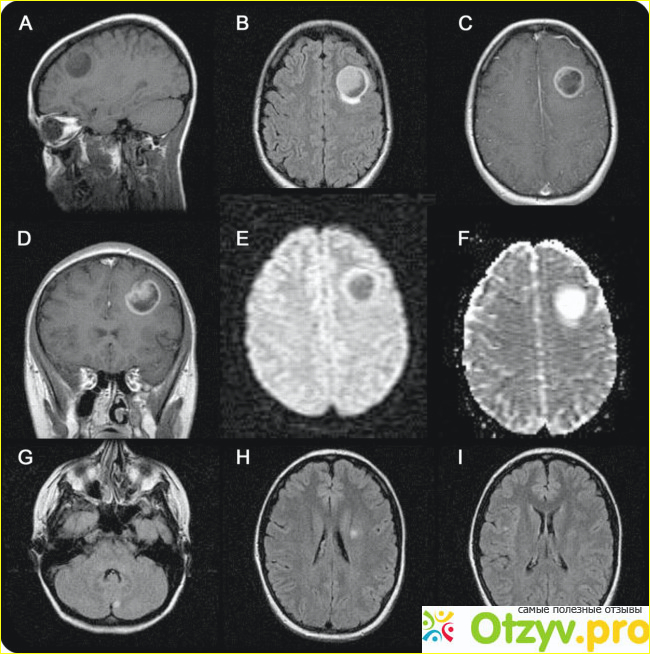

В странах поссоветского пространства стоят преимущественно Низкопольные МРТ аппараты, которые имеют напряженность в 0,-0,5 Теслы. Их отличает простота в эксплуатации и экономичность. И это в основном довольно древние машинки. Преимущество их в том, что стоимость обследования очень невысокая и доступна большинству. Грубо говоря, такие магниты довольно примитивны и их можно применить разве что, чтобы диагностировать какую-то грубую патологию, например обнаружить межпозвоночную грыжу или опухоль головного мозга, если та имеет внушительные размеры. Такие аппараты на низкопольных магнитах плохи в решении большинства кардиологических проблем сложно трактографировать проводящие пути, а некоторые исследования, например выяснить кортикальную активность – вовсе недостижимы.

Золотой стандарт в проведении исследований – это применение высокопольных магнитов, которые работают на криогенной гелиевой системе. Они имеют уровень напряженности от 1 до 1,5 теслы. Такой аппарат довольно информативный и поэтому именно ему следует отдать предпочтение. Более современные аппараты будут существенно удорожать проведение процедуры МРТ. На аппарате с высокопольным магнитом можно сканировать все тело за одно прохождение.

Конечно, максимальная информативность получаемых данных будет именно на аппарата со сверхвысокопольном магните, которые имеют индуктивность около 3 тесла. Их часто используют ученые в научных исследованиях. Но цена таких обследований будет очень высока и многим просто может оказаться недоступной для бюджета.